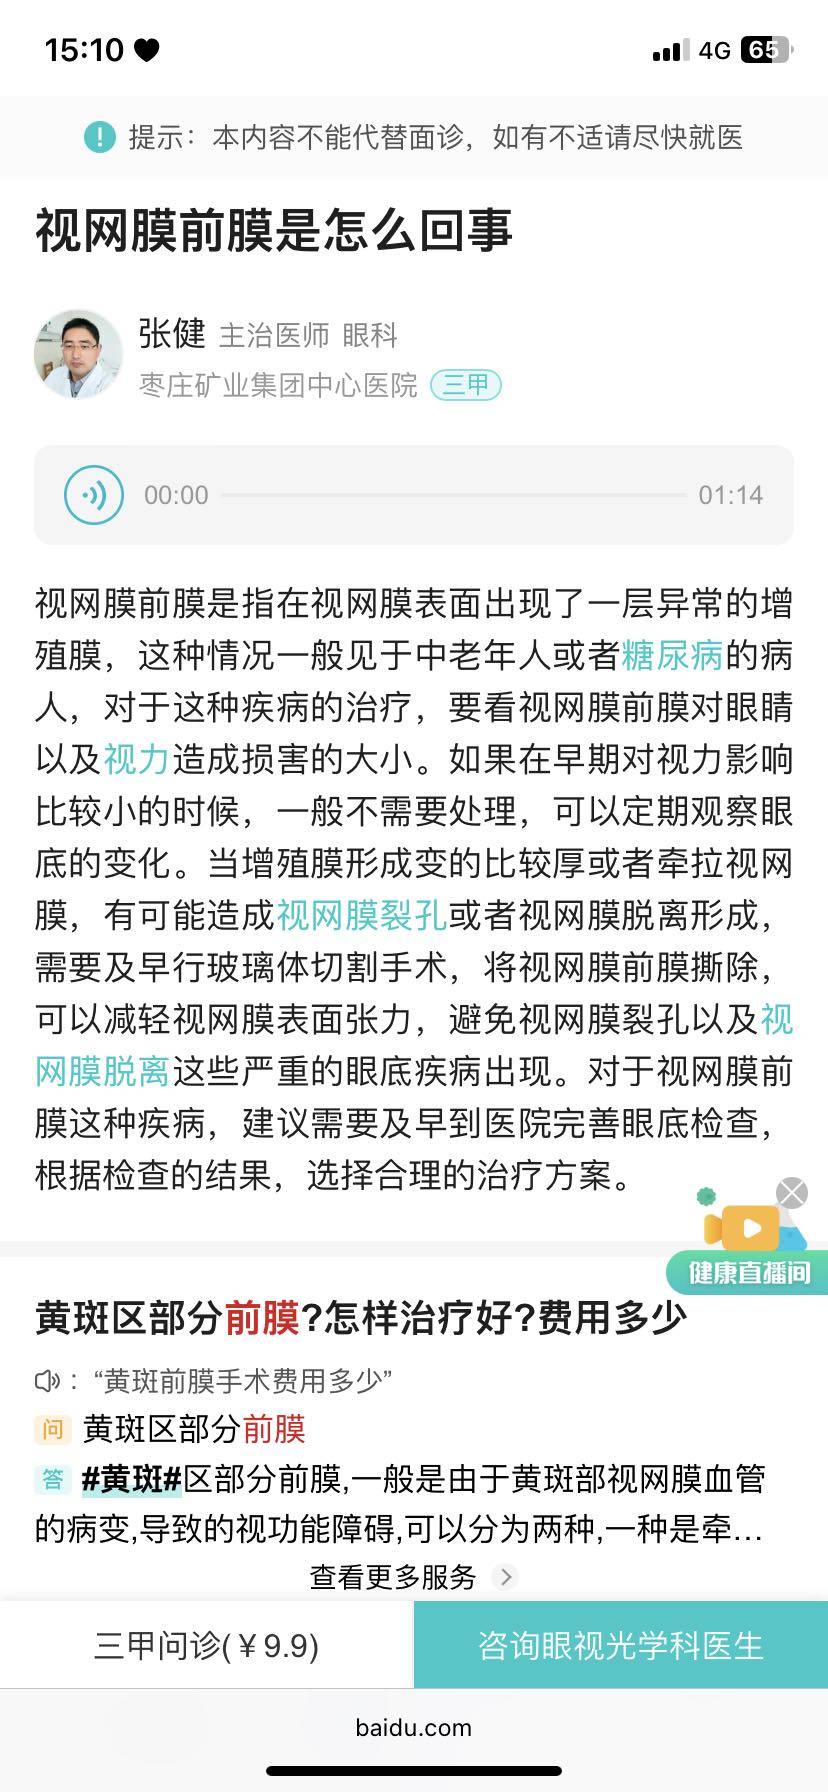

然后回去路上百度了一下

emmmm查了一下,这玩意只能等严重了之后做手术割掉……

至今我不知道是个人原因还是狼疮吃药的原因导致。打算下个月复查问问风湿科主治,如果纷乐影响能不能停纷乐😭